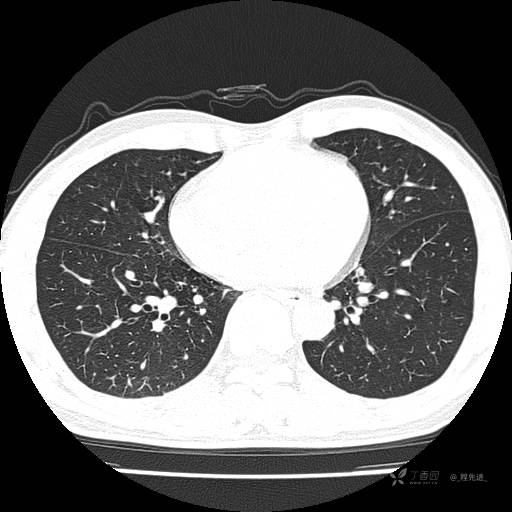

2月特别精彩病例|咳嗽、咳痰20余天,典型病例分享【结果已公布】

患者年龄:51岁

主诉:咳嗽、咳痰20余天

简要病史:20余天前开始出现咳嗽、咳痰症状,阵发性刺激性咳,白色粘痰,不易咳出,无发热,无咯血,无恶心、呕吐等不适,未诊治,咳嗽、咳痰症状持续存在。

体格检查:T:36.3 ℃ P:79 次/分 R:20 次/分 BP:128/64 mmHg,神志清楚,呼吸平稳,双肺呼吸音粗,右下肺闻及细湿性啰音。心率79次/分,节律整齐,各瓣膜听诊区未闻及病理性杂音。腹部未见异常,双下肢无水肿。

辅助检查:我院门诊胸部CT示:如下。心电图:窦性心律;正常心电图。